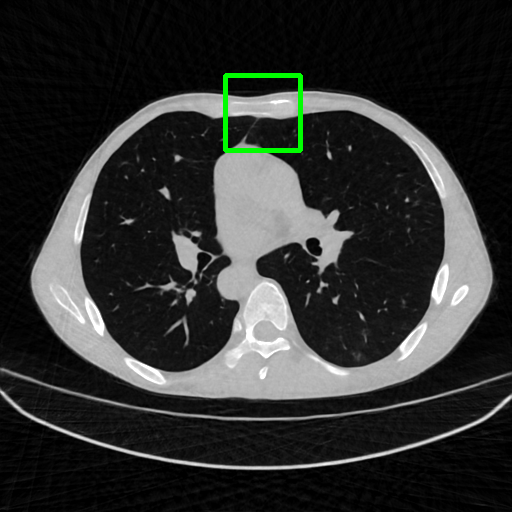

Qualitative comparison. We also visualize the reconstructed images of these methods in Fig. 4 with = [72, 96 ,144] (See more visualizations in Appendix). In all three rows, our DuDoTrans shows better detail recovery, and sparse-view artifacts are suppressed. Further, when decreasing , where raw sinograms are too messy to be restored and low-quality images from FBP are too hard to capture global features, Transformer-based models exhibit reduced performance. The phenomena suggests that we should design suitable structures with the Transformer and CNNs, facing with different cases.

Ground Truth

FBP

FBPConvNet

DuDoNet

ImgTrans

DuDoTrans